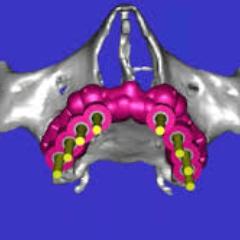

Chirurgia guidata

Attraverso la chirurgia guidata vengono realizzati impianti e forature chirurgiche in modo digitale ottenendo risultati altamente accurati, sicuri e prevedibili, direttamente il laboratorio.